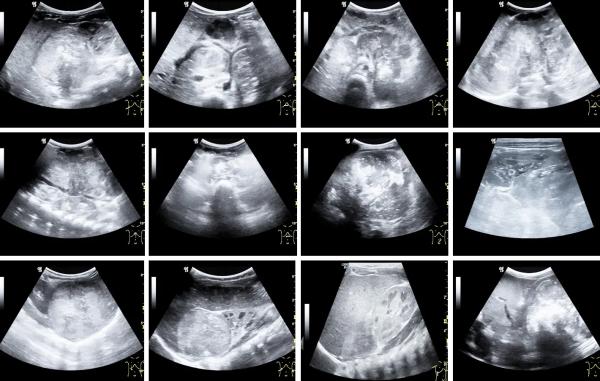

Метод также может быть использован для мониторинга объемно-структурных изменений в опухоли после начала лечения. Это позволяет онкологам оценить эффективность лечения и решить, нужны ли дополнительные меры. Сонографические варианты первично диагностируемой гепатобластомы представлены на рисунке 1.

Рисунок 1. Сонографические варианты первично диагностируемой гепатобластомы.Представлены на снимках отграниченной в значительной части контура в виде узла либо имеющей диффузный рост солидной опухолью печени больших размеров.